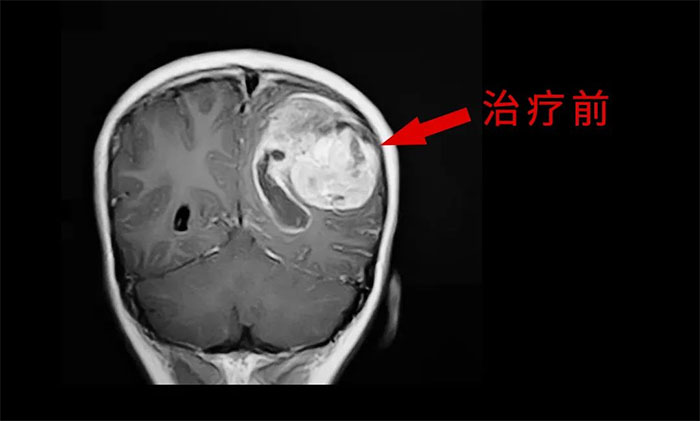

近日,河南31歲的吳女士(化名)過了陽歷年就開始嗜睡,斷斷續(xù)續(xù)地持續(xù)了20多天。一開始家人以為是帶孩子太累了需要休息,讓人沒想到的是,大年初二她醒后開始說胡話。又過了幾天,竟不認(rèn)識人了,出現(xiàn)了嚴(yán)重的意識障礙。當(dāng)?shù)蒯t(yī)院檢查顯示,她顱內(nèi)長了膠質(zhì)瘤。吳女士也因嗜睡20余天后,智商低如幼女而登上了熱搜榜。而造成這一切的“罪魁禍?zhǔn)?rdquo;——腦膠質(zhì)瘤,也成了時下社會熱議的焦點(diǎn)。

膠質(zhì)瘤是來源于神經(jīng)系統(tǒng)膠質(zhì)細(xì)胞和神經(jīng)元細(xì)胞腫瘤的統(tǒng)稱,約占顱內(nèi)腫瘤的40%-50%,是最常見的原發(fā)性顱內(nèi)腫瘤,也是顱內(nèi)最常見的惡性腫瘤,屬于神經(jīng)外科治療中最棘手的難治性腫瘤之一。于耀宇主任談到。

由于腦膠質(zhì)瘤具有侵襲性、浸潤性生長的特性,高級別膠質(zhì)瘤與正常腦組織無明確邊界,難以大范圍徹底切除,殘留的腫瘤細(xì)胞成為日后復(fù)發(fā)的根源,因此腦膠質(zhì)瘤具有高復(fù)發(fā)率、高致殘率的特征,嚴(yán)重影響患者的生活質(zhì)量和生存周期,堪稱“大腦殺手”。

目前,腦膠質(zhì)瘤的治療方面,倡導(dǎo)MDT多學(xué)科診治,神經(jīng)外科、影像科、放射治療科、腫瘤科、病理科和康復(fù)科等多學(xué)科合作,遵循循證醫(yī)學(xué)原則,優(yōu)化和規(guī)范治療方案,采取個體化綜合治療,以期達(dá)到最大治療效益,盡可能延長患者的無進(jìn)展生存期(PFS) 和總生存期(OS),提高生存質(zhì)量。

外科手術(shù)往往是膠質(zhì)瘤治療的第一步。手術(shù)原則是在最大范圍安全切除(maximal safe resection)腫瘤的同時,保護(hù)神經(jīng)功能區(qū)。以解除占位征象和緩解顱內(nèi)高壓癥狀;解除或緩解因腦膠質(zhì)瘤引發(fā)的相關(guān)癥狀;獲得病理組織和分子病理,明確診斷;降低腫瘤負(fù)荷,為后續(xù)綜合治療提供條件。